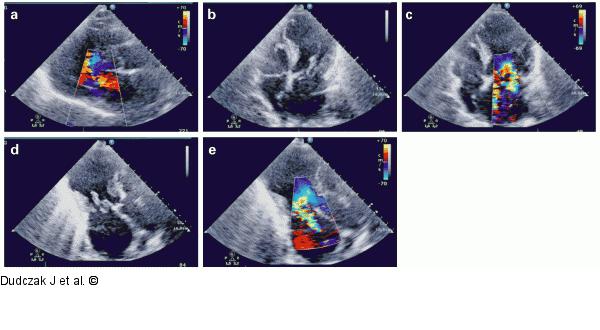

Abbildung 3a-e: Echokardiographie Echokardiographie. (a–e): Hypo-/Akinesie im Bereich der Vorderwand und ein Abriss des anterioren Papillarmuskels sind zu sehen. |

Echokardiographie. (a–e): Hypo-/Akinesie im Bereich der Vorderwand und ein Abriss des anterioren Papillarmuskels sind zu sehen. |